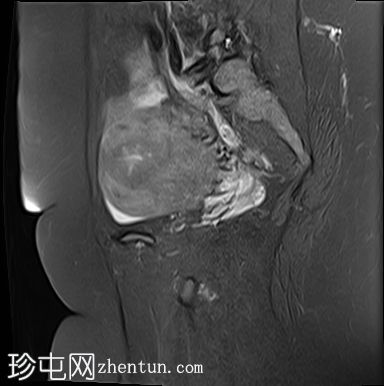

矢状位

T2脂肪抑制像

子宫前倾且体积增大,交界区呈边界不清、弥漫性对称性增厚。T2加权像和T2脂肪抑制像均显示条纹状高信号,无异常强化或扩散受限。

本病例展示了弥漫性子宫腺肌症的典型MRI特征,包括交界区弥漫性增厚和T2加权像上呈条纹状高信号区域。